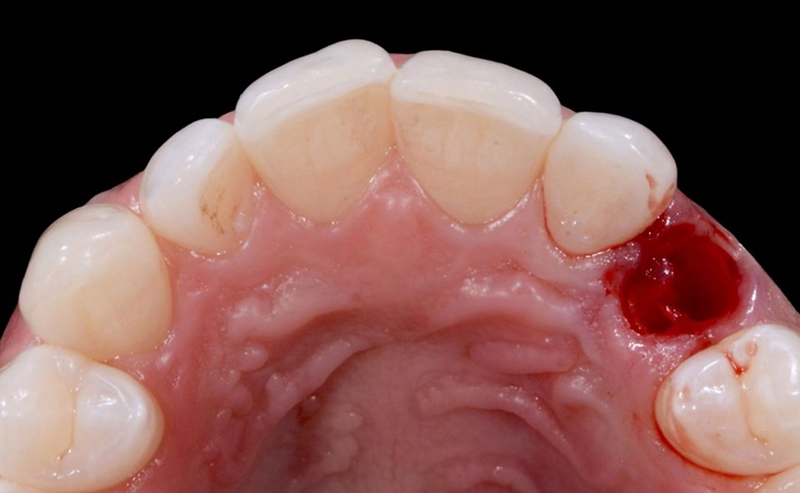

患者在犬尖对应的区域进行了局部麻醉浸润(图25)。乳牙的拔除过程非常简单,牙根几乎完全被吸收(图26-28)。

Fig. 28: Occlusal view of the extraction socket.

拔出后,将手术导板放入患者的口腔中,因为通过在特定位置创建的窗口来验证其稳定性和精度非常重要(图29)。